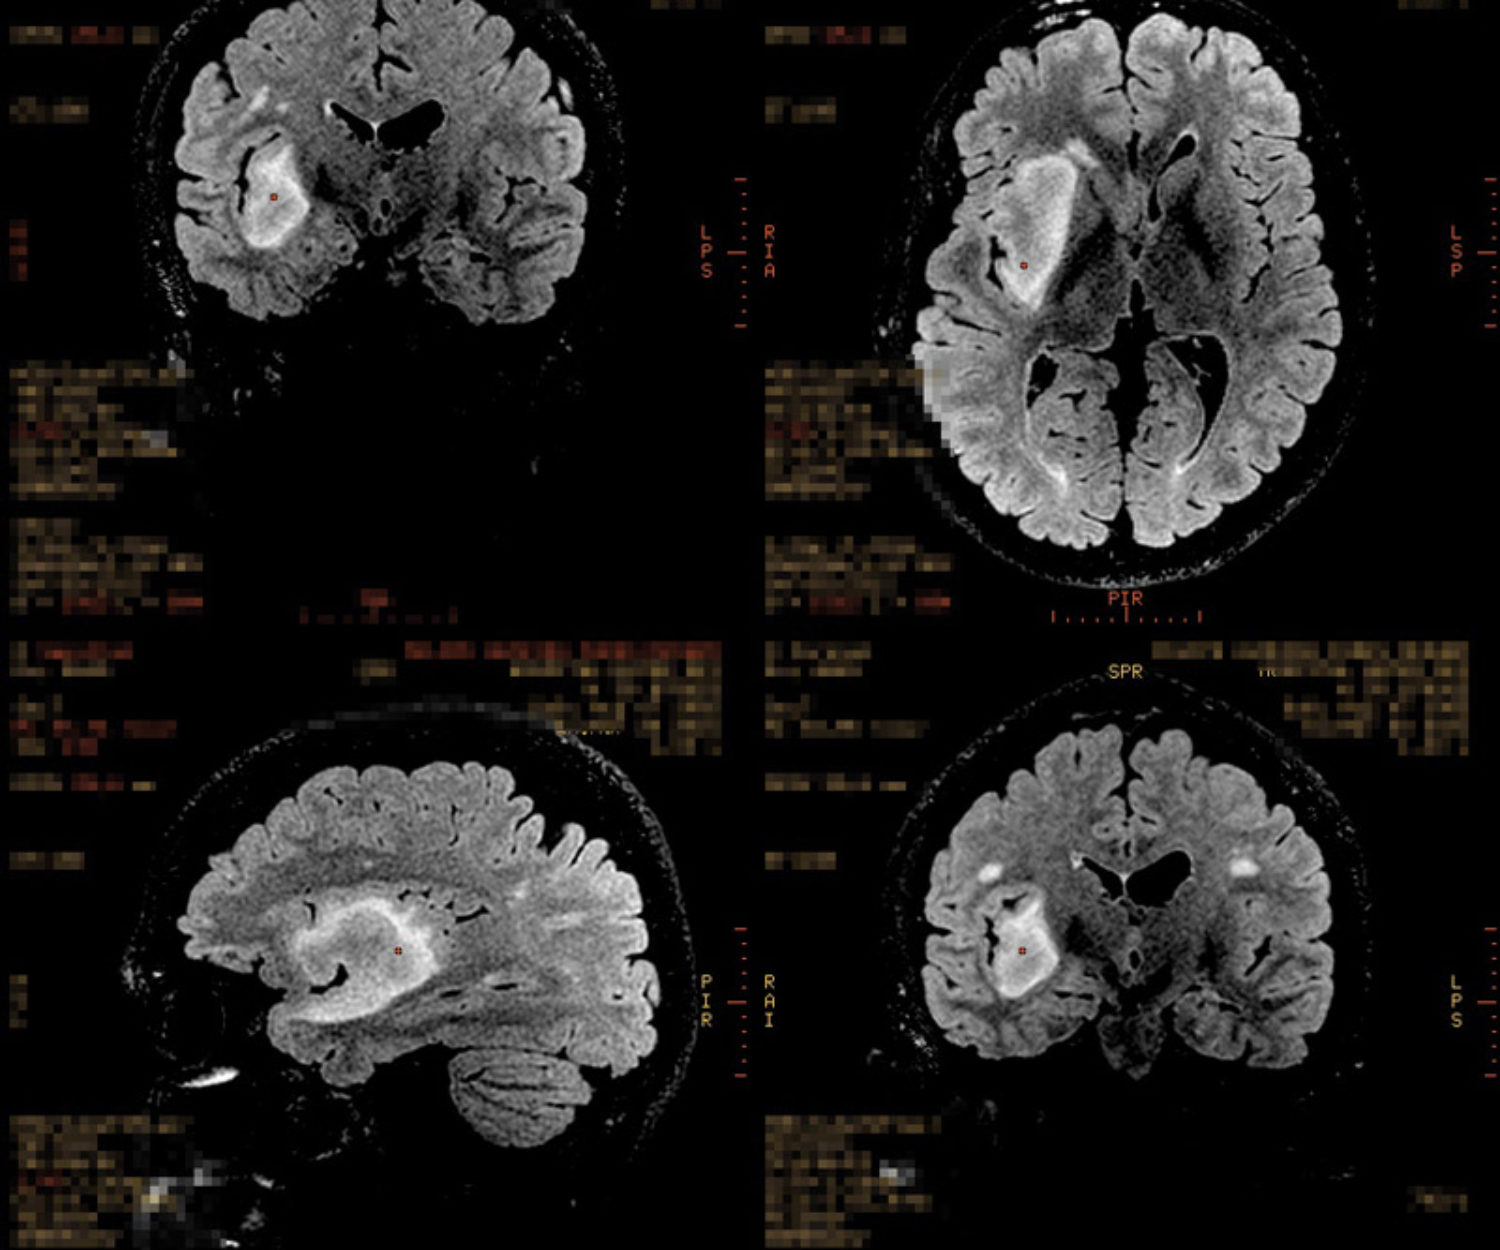

O caminho se faz é caminhando 03 maio 2025 Quatro anos Em 3 de maio de 2021, minha cabeça foi aberta para retirar um tecido tumoral de 5,5 cm x 4,4… Felipe 6 Comments